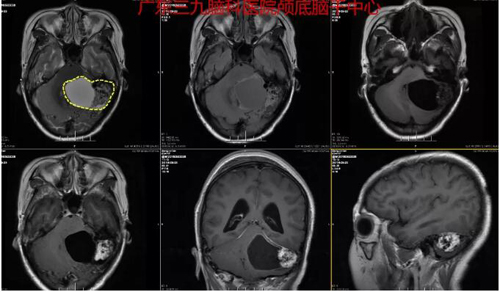

入院后完善头颅MRI和CTA等相关检查,考虑血管母细胞瘤可能,左侧小脑半球占位性病变,异常染色区域大小约4.0cm×3.0cm×2.0cm;CTA检查示左侧小脑半球囊性占位性病变内未见异常血管影,病变偏外侧示一团状粗细不均异常血管影,引流静脉汇入左侧乙状窦,左侧大脑后动脉受推挤。由张良主刀在显微镜下为吴女士做了“左侧小脑占位病变切除术”,术程顺利,病理报告示:(左侧小脑)血管母细胞瘤WHOⅠ级。

图2:术前MR示左侧小脑半球占位性病变,考虑血管母细胞瘤可能,异常染色区域大小约4.0cm×3.0cm×2.0cm